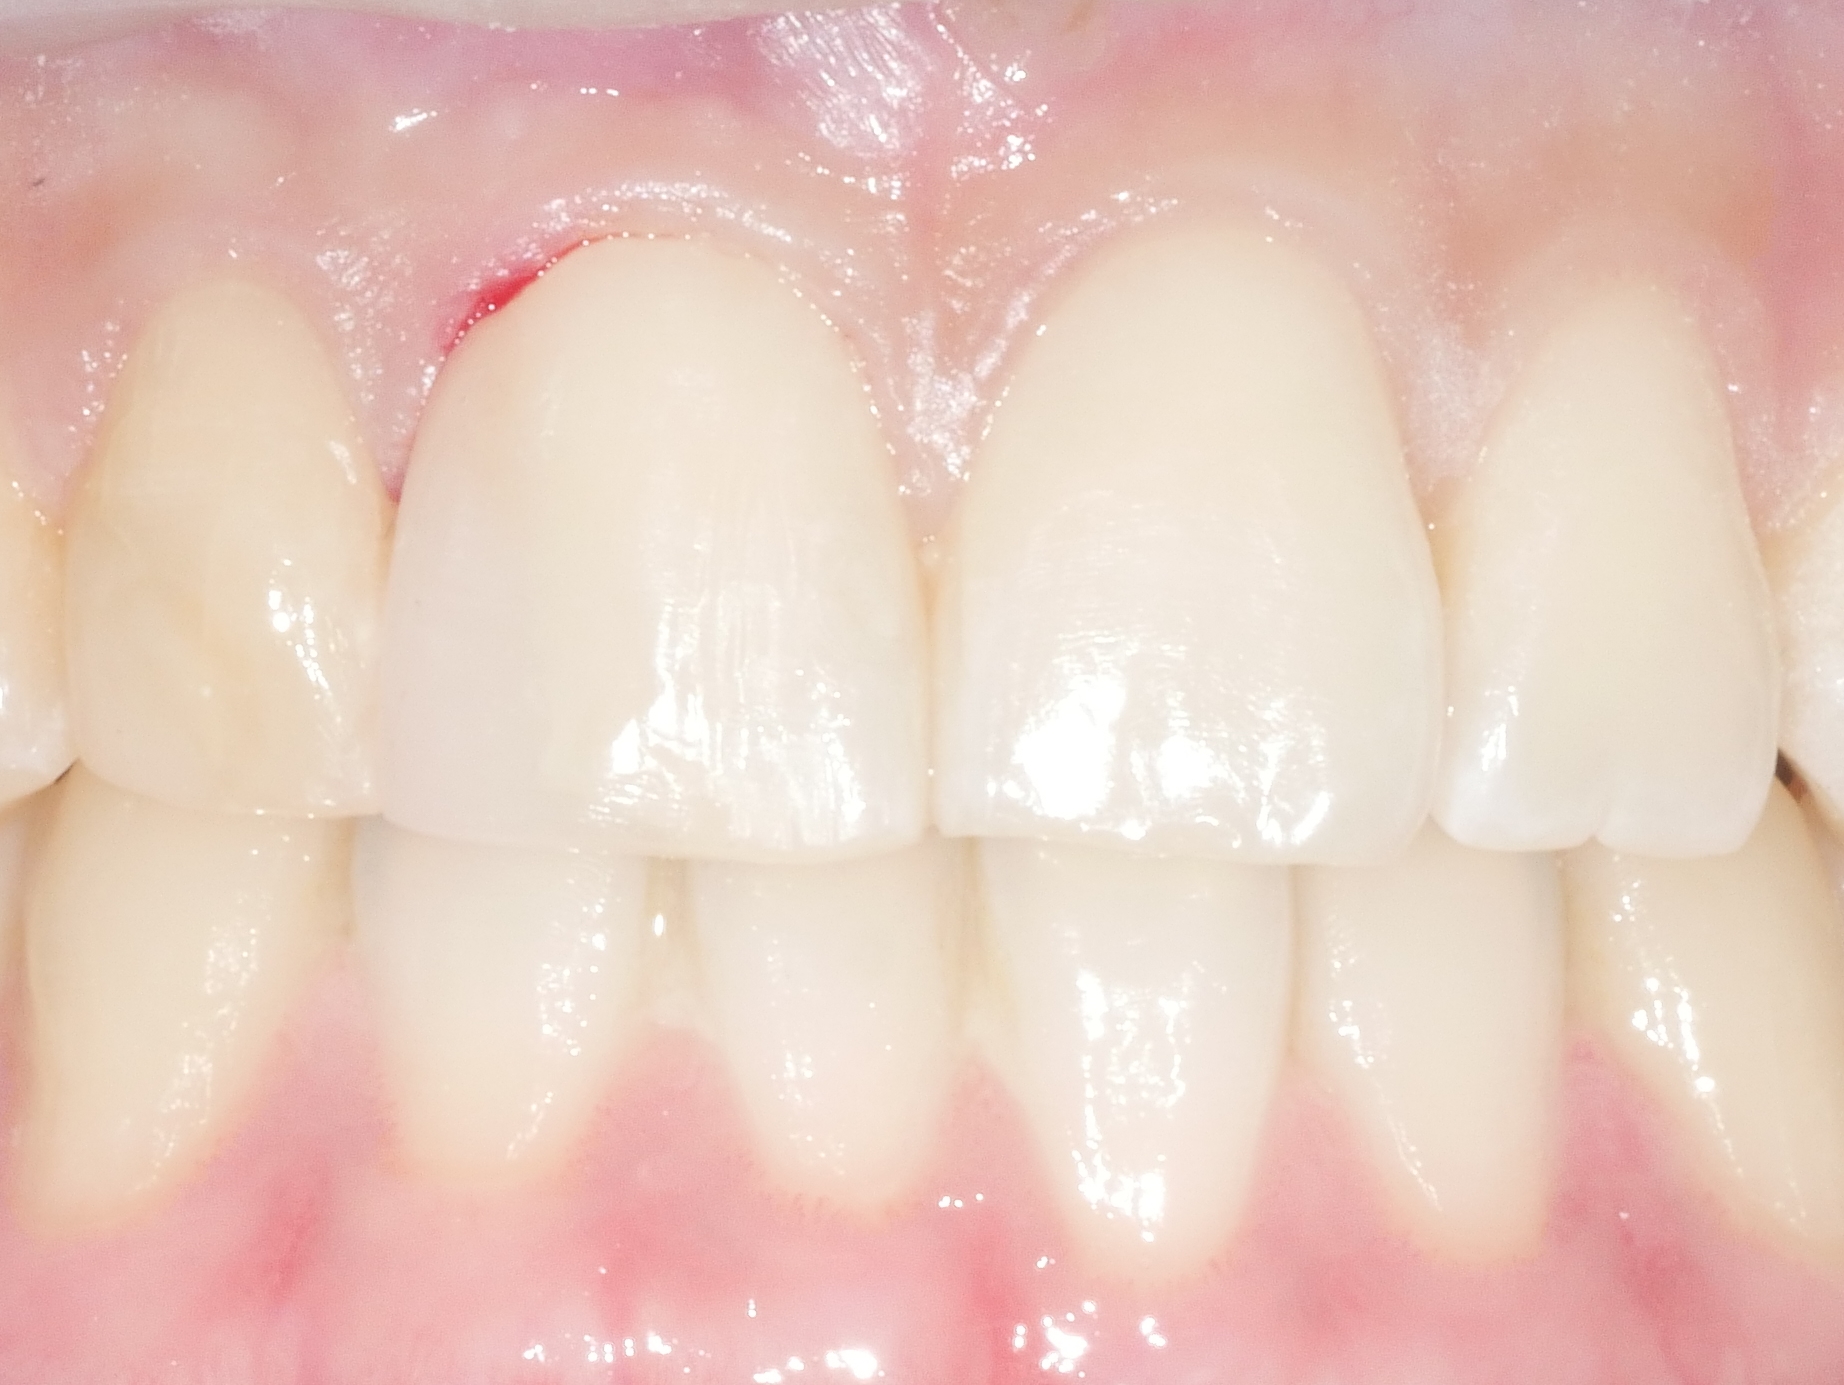

CASE.03 앞니 충치 레진치료

• 앞니 충치 레진치료

앞니에 생긴 충치와 파절부위를 레진으로 당일 치료

치료전 2025.10.23 / 치료후 2025.10.23